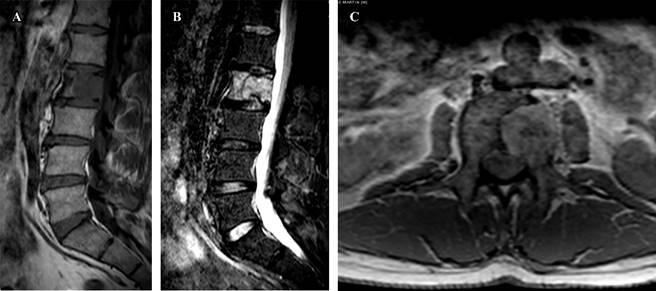

El paciente aporta una tomografía axial computarizada (TAC) y una resonancia magnética nuclear (RMN) (Figuras 1 y 2) que muestran una lesión lítica inespecífica en la espinosa de T1 y otra lesión en el cuerpo vertebral de L2. Ante estos hallazgos, se solicita una gammagrafía y una TAC toracoabdominal y se reprograma al paciente en una semana en consultas. Se realiza la gammagrafía que sólo muestra captación a nivel de ambas lesiones vertebrales. La TAC toracoabdominal informa de un enfisema paraseptal con atelectasias en el lóbulo inferior derecho y un área inespecífica en vidrio deslustrado en el lóbulo medio, sin alteraciones en el parénquima pulmonar ni otras lesiones a nivel abdominal.

Figura 2: A y B) Cortes de resonancia magnética nuclear (RMN) sagital en T1 y STIR que muestran una masa tumoral en el cuerpo vertebral de L2. C) Corte de RMN en axial que evidencia la invasión tumoral del hemicuerpo izquierdo de L2.